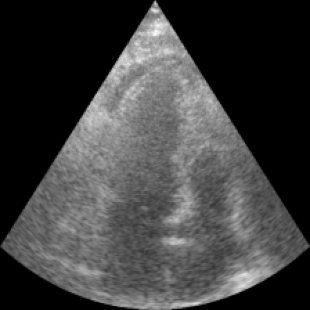

We propose a novel approach that adapts hierarchical vision foundation models for real-time ultrasound image segmentation. Existing ultrasound segmentation methods often struggle with adaptability to new tasks, relying on costly manual annotations, while real-time approaches generally fail to match state-of-the-art performance. To overcome these limitations, we introduce an adaptive framework that leverages the vision foundation model Hiera to extract multi-scale features, interleaved with DINOv2 representations to enhance visual expressiveness. These enriched features are then decoded to produce precise and robust segmentation. We conduct extensive evaluations on six public datasets and one in-house dataset, covering both cardiac and thyroid ultrasound segmentation. Experiments show that our approach outperforms state-of-the-art methods across multiple datasets and excels with limited supervision, surpassing nnUNet by over 20\% on average in the 1\% and 10\% data settings. Our method achieves $\sim$77 FPS inference speed with TensorRT on a single GPU, enabling real-time clinical applications.